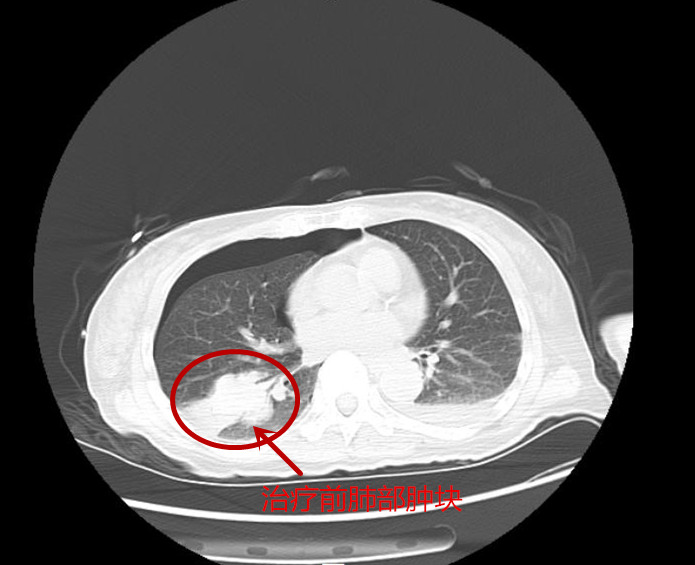

经过一段时间的治疗,张英病情稳定,医生建议可以出院在家服药治疗,但需定期复诊。6月9日患者顺利出院。在精准治疗满两个多月后,8月初,张英入院复查,经过对肺部、头部以及胸椎等处的影像学检查,结果显示肺部肿块及头部的病灶对比第一次入院时缩小了50%以上,胸9椎体的骨质破坏也得到了控制。得知结果后,她激动地对医护人员说:“感谢捷克论坛 肿瘤二科给了我第二次生命,也希望有同样遭遇的病友通过他们的宣传,能重获新生!”